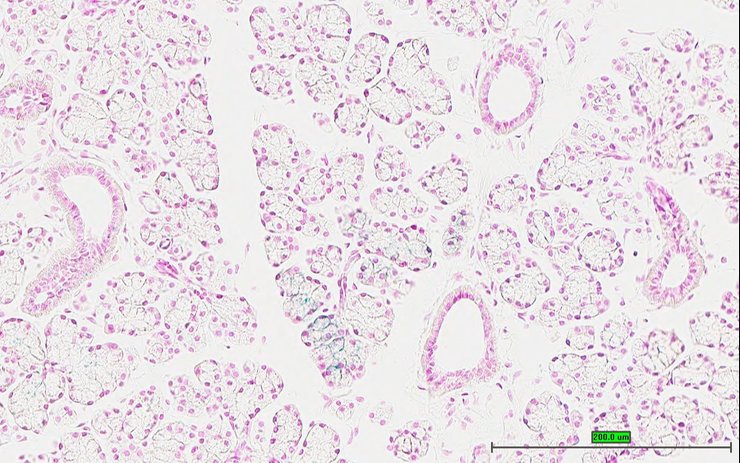

TS28: lung Present UC Davis_1880191

Specimen UC Davis_1880192: postnatal adult; Prpf18tm1.1(KOMP)Vlcg/Prpf18+ (more )

Structure Level Pattern Image Note

TS28: lung Present UC Davis_1880192

TS28: lung Present UC Davis_1880249

Specimen UC Davis_1880250: postnatal adult; Prpf18tm1.1(KOMP)Vlcg/Prpf18+ (more )

TS28: lung Present UC Davis_1880250

Specimen UC Davis_1880251: postnatal adult; Prpf18tm1.1(KOMP)Vlcg/Prpf18+ (more )

TS28: lung Present UC Davis_1880251